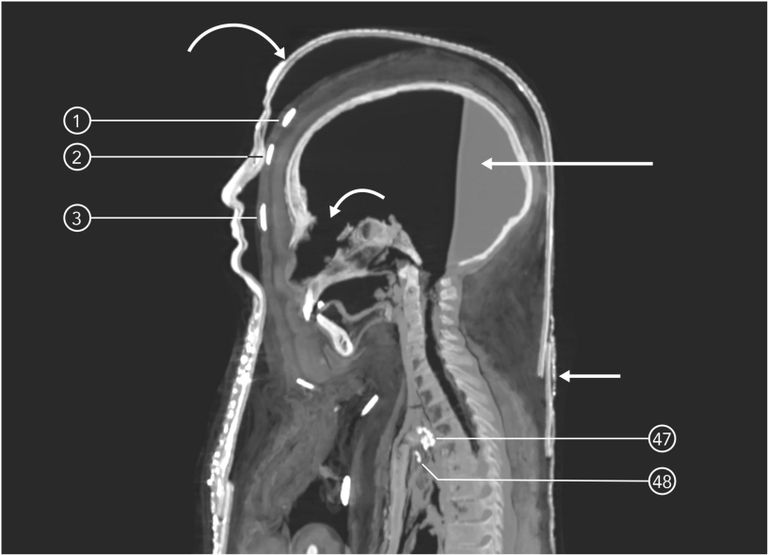

ما هي ملامحه؟

بعد إزالة اللفائف افتراضيًا اتضح الوجه وملامحه، الأنف متوسط وليس دقيقًا أو غليظًا، والعينان كانتا شبه مفتوحتين، هي في المجمل ملامح صبي مصري.

بالاطلاع تبين أن التحنيط كان على مستو عال، خاصةً مع إزالة المخ من الأنف والأحشاء من فتحة أسفل البطن، ووضع الحشوات والمواد الراتنجية.

في بادئ الأمر يتم غلق فتحات الأنف والفم والشرج وغيرها لمنع دخول الحشرات، بعدما يجري وضع اللفائف، ثم يتم وضع الجسد في التابوت، وفي وقت لاحق أضافوا خطوة جديدة تتمثل في وضع التابوت داخل سلاسل من التوابيت لمزيد من الحماية.